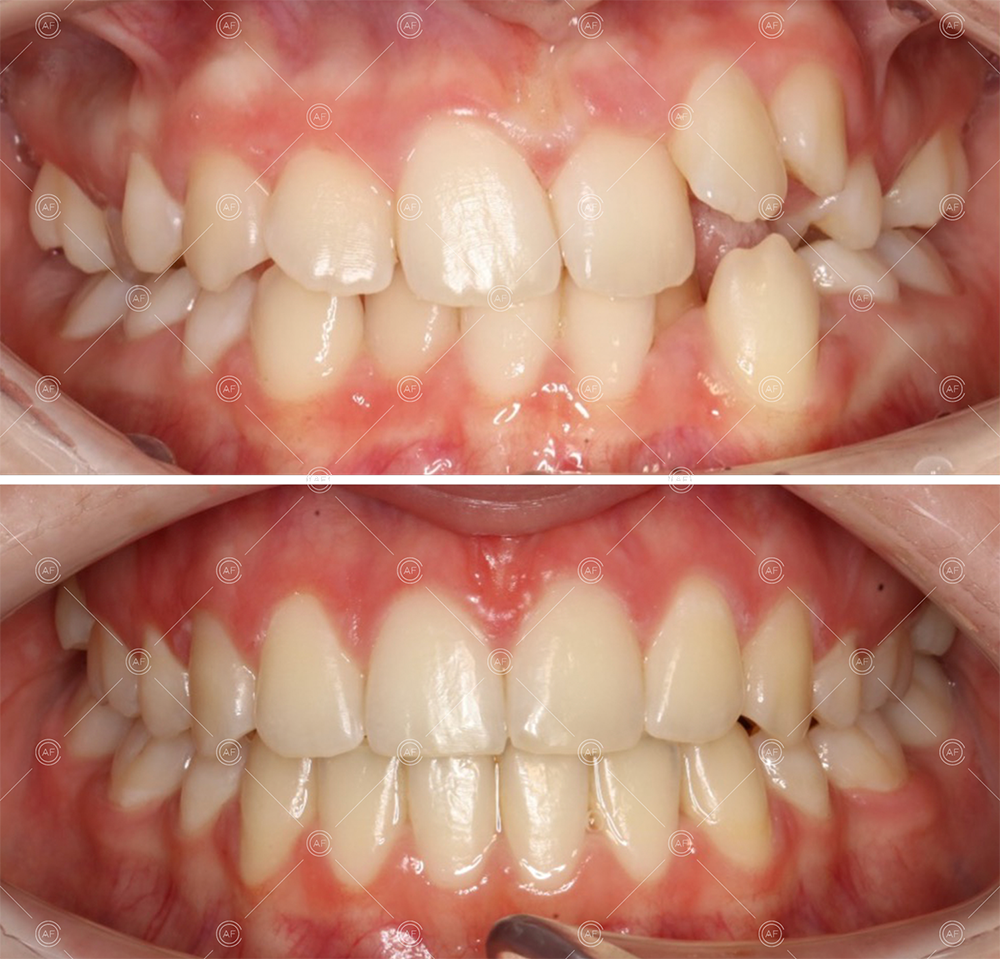

Treatment progressed by starting with thin, flexible nickel titanium archwires of a round diameter, transitioning to a rectangular nickel titanium archwire before eventually working up to a working archwire (1925 stainless steel).

Residual space from the extractions were closed using upper and lower nickel titanium closing coils. Class 2 elastics were used to facilitate space closure in order to gain class 1 buccal segments.